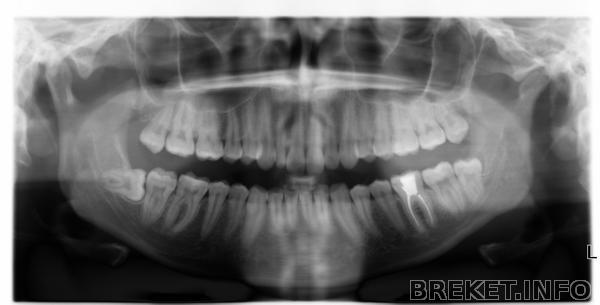

Сделали сегодня снимок. Теперь стало очевидно почему у меня поехал нижний ряд зубов.... Прямо не восьмерка а ракета!))

Ура! Поздравляю с приобретением ортофея))) Восьмерка прям как у меня была